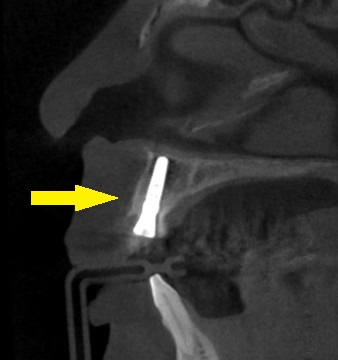

下の写真が手術前後のCTです。